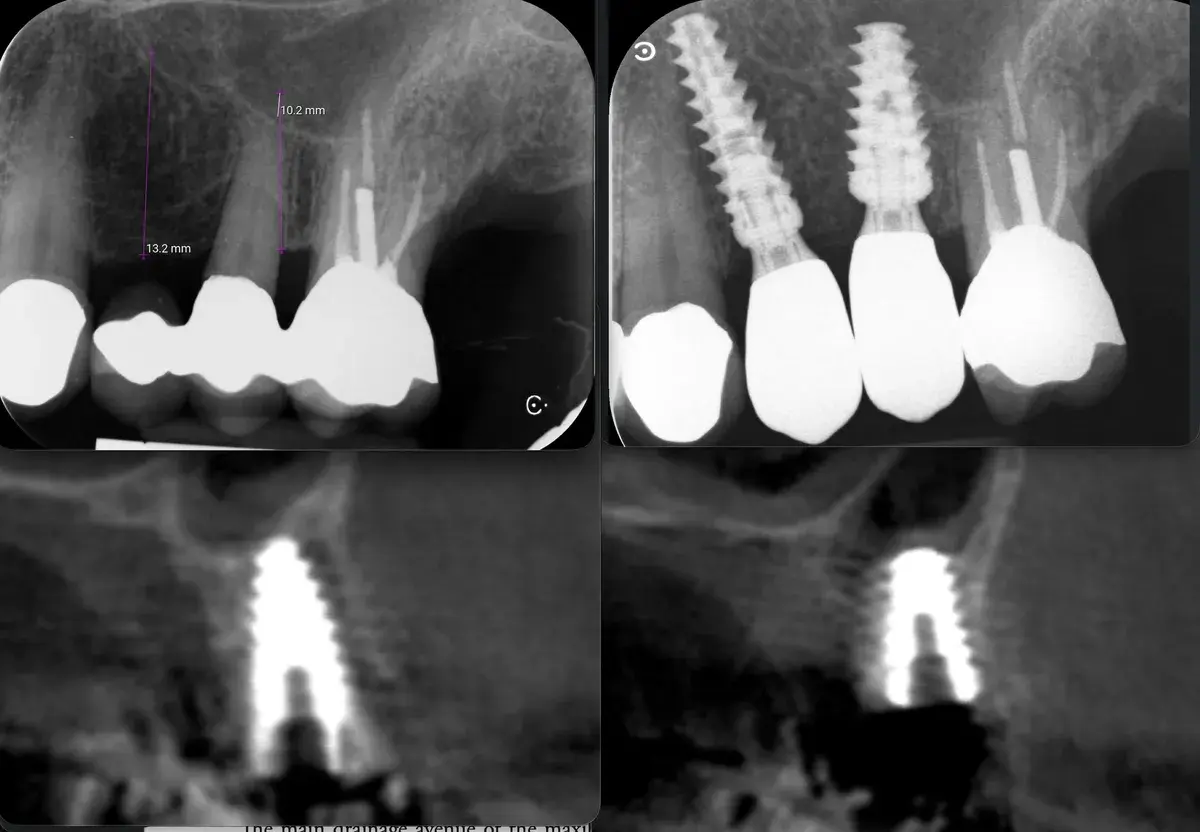

Espansione osteo-mucosa in 4.6: dal difetto severo alla corona definitiva

Cresta atrofica in zona 4.6 con difetto osteo-mucoso e cheratinizzata quasi assente: Bonebending 4.0 e impianto in unica seduta. Risultato a 3 mesi.

Caso clinico: espansione crestale ERE con impianto immediato e rigenerazione simultanea. Da ponte fallito a impianto in un'unica seduta.

Caso clinico LMSF graftless: due impianti a 1.6/1.5 con espansori a vite calibrati. Gestione localizzata del seno mascellare, senza innesto.